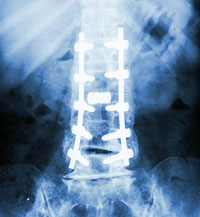

Over the years, I experienced several lumbar injuries (run over twice, once on my scoot in 1980 and bicycle in 1984). I had another significant debilitating injury in 2010 that required Reconstructive Lumbar Surgery. They fixed me up, sort of, and the Orthopods installed some really cool Titanium hardware to boot. The recovery took longer than anticipated, a full five years, and I finally retired for good in July 2014.

Major Lumbar surgery was scheduled for January 11th, 2011 (1-11-11; the date has a nice ring to it). The operation was a three-level lumbar discectomy, laminectomy, and lumbar fusion. And I got the Bonus deal. The surgery came complete with Titanium rods and screws that fastened the three lowest spinal levels to my pelvis. I am a card-carrying member of the "I got metal hardware in my body, club," so when going through TSA for a flight, I light up the detectors. I move a little slower these days and am very careful to protect my back at all costs.